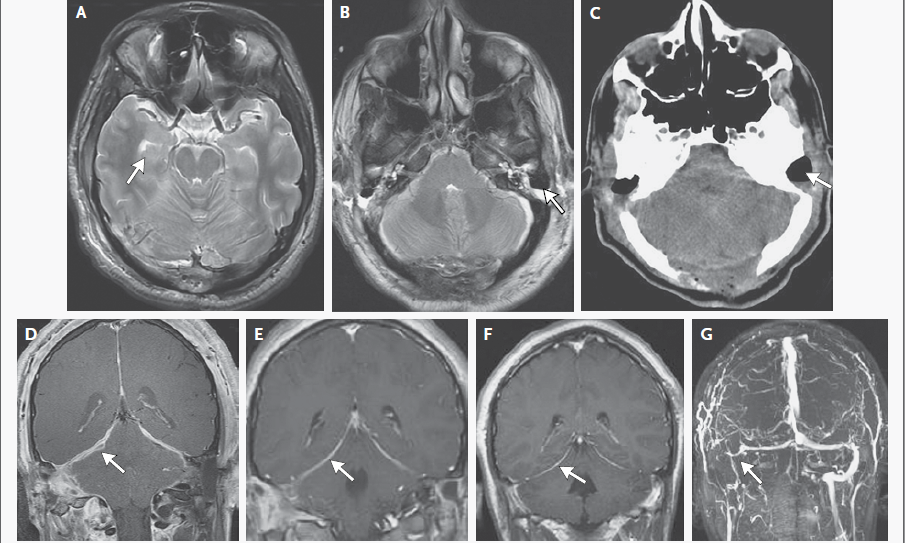

El examen de las muestras de biopsia de la etmoidal posterior izquierda y senos esfenoidales mostraron mucosa nasosinusal con un tejido linfoide denso subyacente en un fondo de la fibrosis. Las células linfoides eran grandes, y la tinción inmunohistoquímica para CD20, un antígeno de células B, fue positivo, lo que confirma el diagnóstico de linfoma difuso de células B grandes (Figura 3A, 3B y 3C).

Figura 3

Biopsia muestras de la Izquierda Posterior etmoides y esfenoides senos

En la tinción con hematoxilina y eosina, las muestras de biopsia del etmoides posterior izquierda y senos esfenoidales revelaron mucosa nasosinusal con un tejido linfoide subyacente infiltrante en un fondo de fibrosis moderada (Panel A). Las células linfoides eran grandes, con núcleos irregulares multilobulados, cromatina vesicular y nucleolos prominentes ocasionales (Grupo B). La tinción inmunohistoquímica para CD20 fue difusamente positiva (Grupo C), lo que confirma el diagnóstico de linfoma difuso de células B. En la tinción inmunohistoquímica adicional, las células tumorales fueron difusamente positiva para CD10 (Panel D) y CD30 (Panel E), y la mayoría de las células tumorales eran de forma variable positiva para el linfoma de células B 2 proteínas (BCL2) (Panel F).

El linfoma difuso de células B representa un grupo de cánceres biológicamente heterogéneos que se pueden dividir morfológica, genética e inmunofenotípicamente y que incluyen ciertas entidades específicas.14 La mayoría de los casos no cumplen los criterios diagnósticos de una de las entidades patológicas específicas y son clasificados como linfoma difuso de células B. Un examen más detallado inmunofenotípico del tumor de esta paciente reveló que las grandes células B fueron positivas para antígenos del centro germinal CD10 y linfoma de células B 6 proteínas (BCL6) y fueron negativos para el post-germinal centro mieloma múltiple marcador oncogén 1 (MUM1, también conocido como factor regulador de interferón 4), los hallazgos que indican que el linfoma es de origen germinal-centro, en lugar de origen nongerminal-centro (Figura 3D) 0,15 mayoría de las células tumorales fueron positivas para la proteína antiapoptótica marcador linfoma de células B (2 BCL2) (Figura 3F), 50% de las células tumorales fueron positivas para el antígeno de proliferación Ki-67, y 10% de las células tumorales fueron positivas para MYC. La ausencia de una alta expresión concurrente de BCL2 y MYC indica que este tumor está en un subgrupo de linfoma difuso de células B que se asocia con un mejor pronóstico, en comparación con el subgrupo de tumores que muestran alta expresión concurrente de MYC y BCL2.16 , 17 Las células tumorales fueron también fuertemente y de forma difusa positivas para CD30, un antígeno de activación (Figura 3E); un ARN en el ensayo de hibridación in situ fue negativo para el virus de Epstein-Barr.